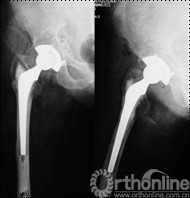

择期行双切口入路(髂腹股沟入路联合髋关节后外侧入路)右腹股沟炎性假瘤切除、骨溶解病灶清除、同种异体颗粒骨植骨、更换负重界面手术治疗。经髂腹股沟入路,见右髂窝内边界清楚,囊壁完整、质中等包块,切开囊壁,可见包块内黄色干酪样物(图7),清除干酪样物,完整切除包块囊壁,见囊壁基底位于髋臼内侧壁并与髋臼通过一直径约5mm骨缺损区相同。术后组织学可见异物吞噬反应(图8)切除髂窝炎性假瘤,经髂骨内板骨缺损区清除髋臼骨溶解病灶,同种异体颗粒骨打压植骨。髋关节后外侧入路更换高分子聚乙烯内衬为高交联聚乙烯内衬,更换钴铬钼股骨头为陶瓷头(图9)。术后2年随访,髋臼骨溶解区新生骨组织替代,髋臼假体无移位、假体稳定固定(图10),CT扫描显示骨溶解区骨长入良好,髋臼骨长入固定(图11)。Harris评分95分。超声复查无关节周围包块。

图11 术后2年随访,CT扫描显示髋臼骨溶解区新生骨组织替代,骨溶解区骨长入良好,髋臼骨长入固定

讨论